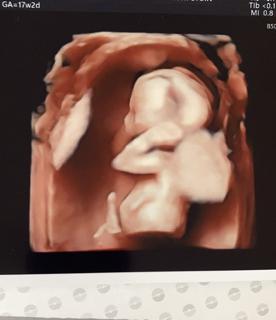

写真:17w2d:ここにゃんさん:超笑顔!

まだまだ小さめでですがエコーを見るといつも暴れてのかというぐらいに動いてます笑

だんだん顔つきも分かってきてるのかな?と思います!